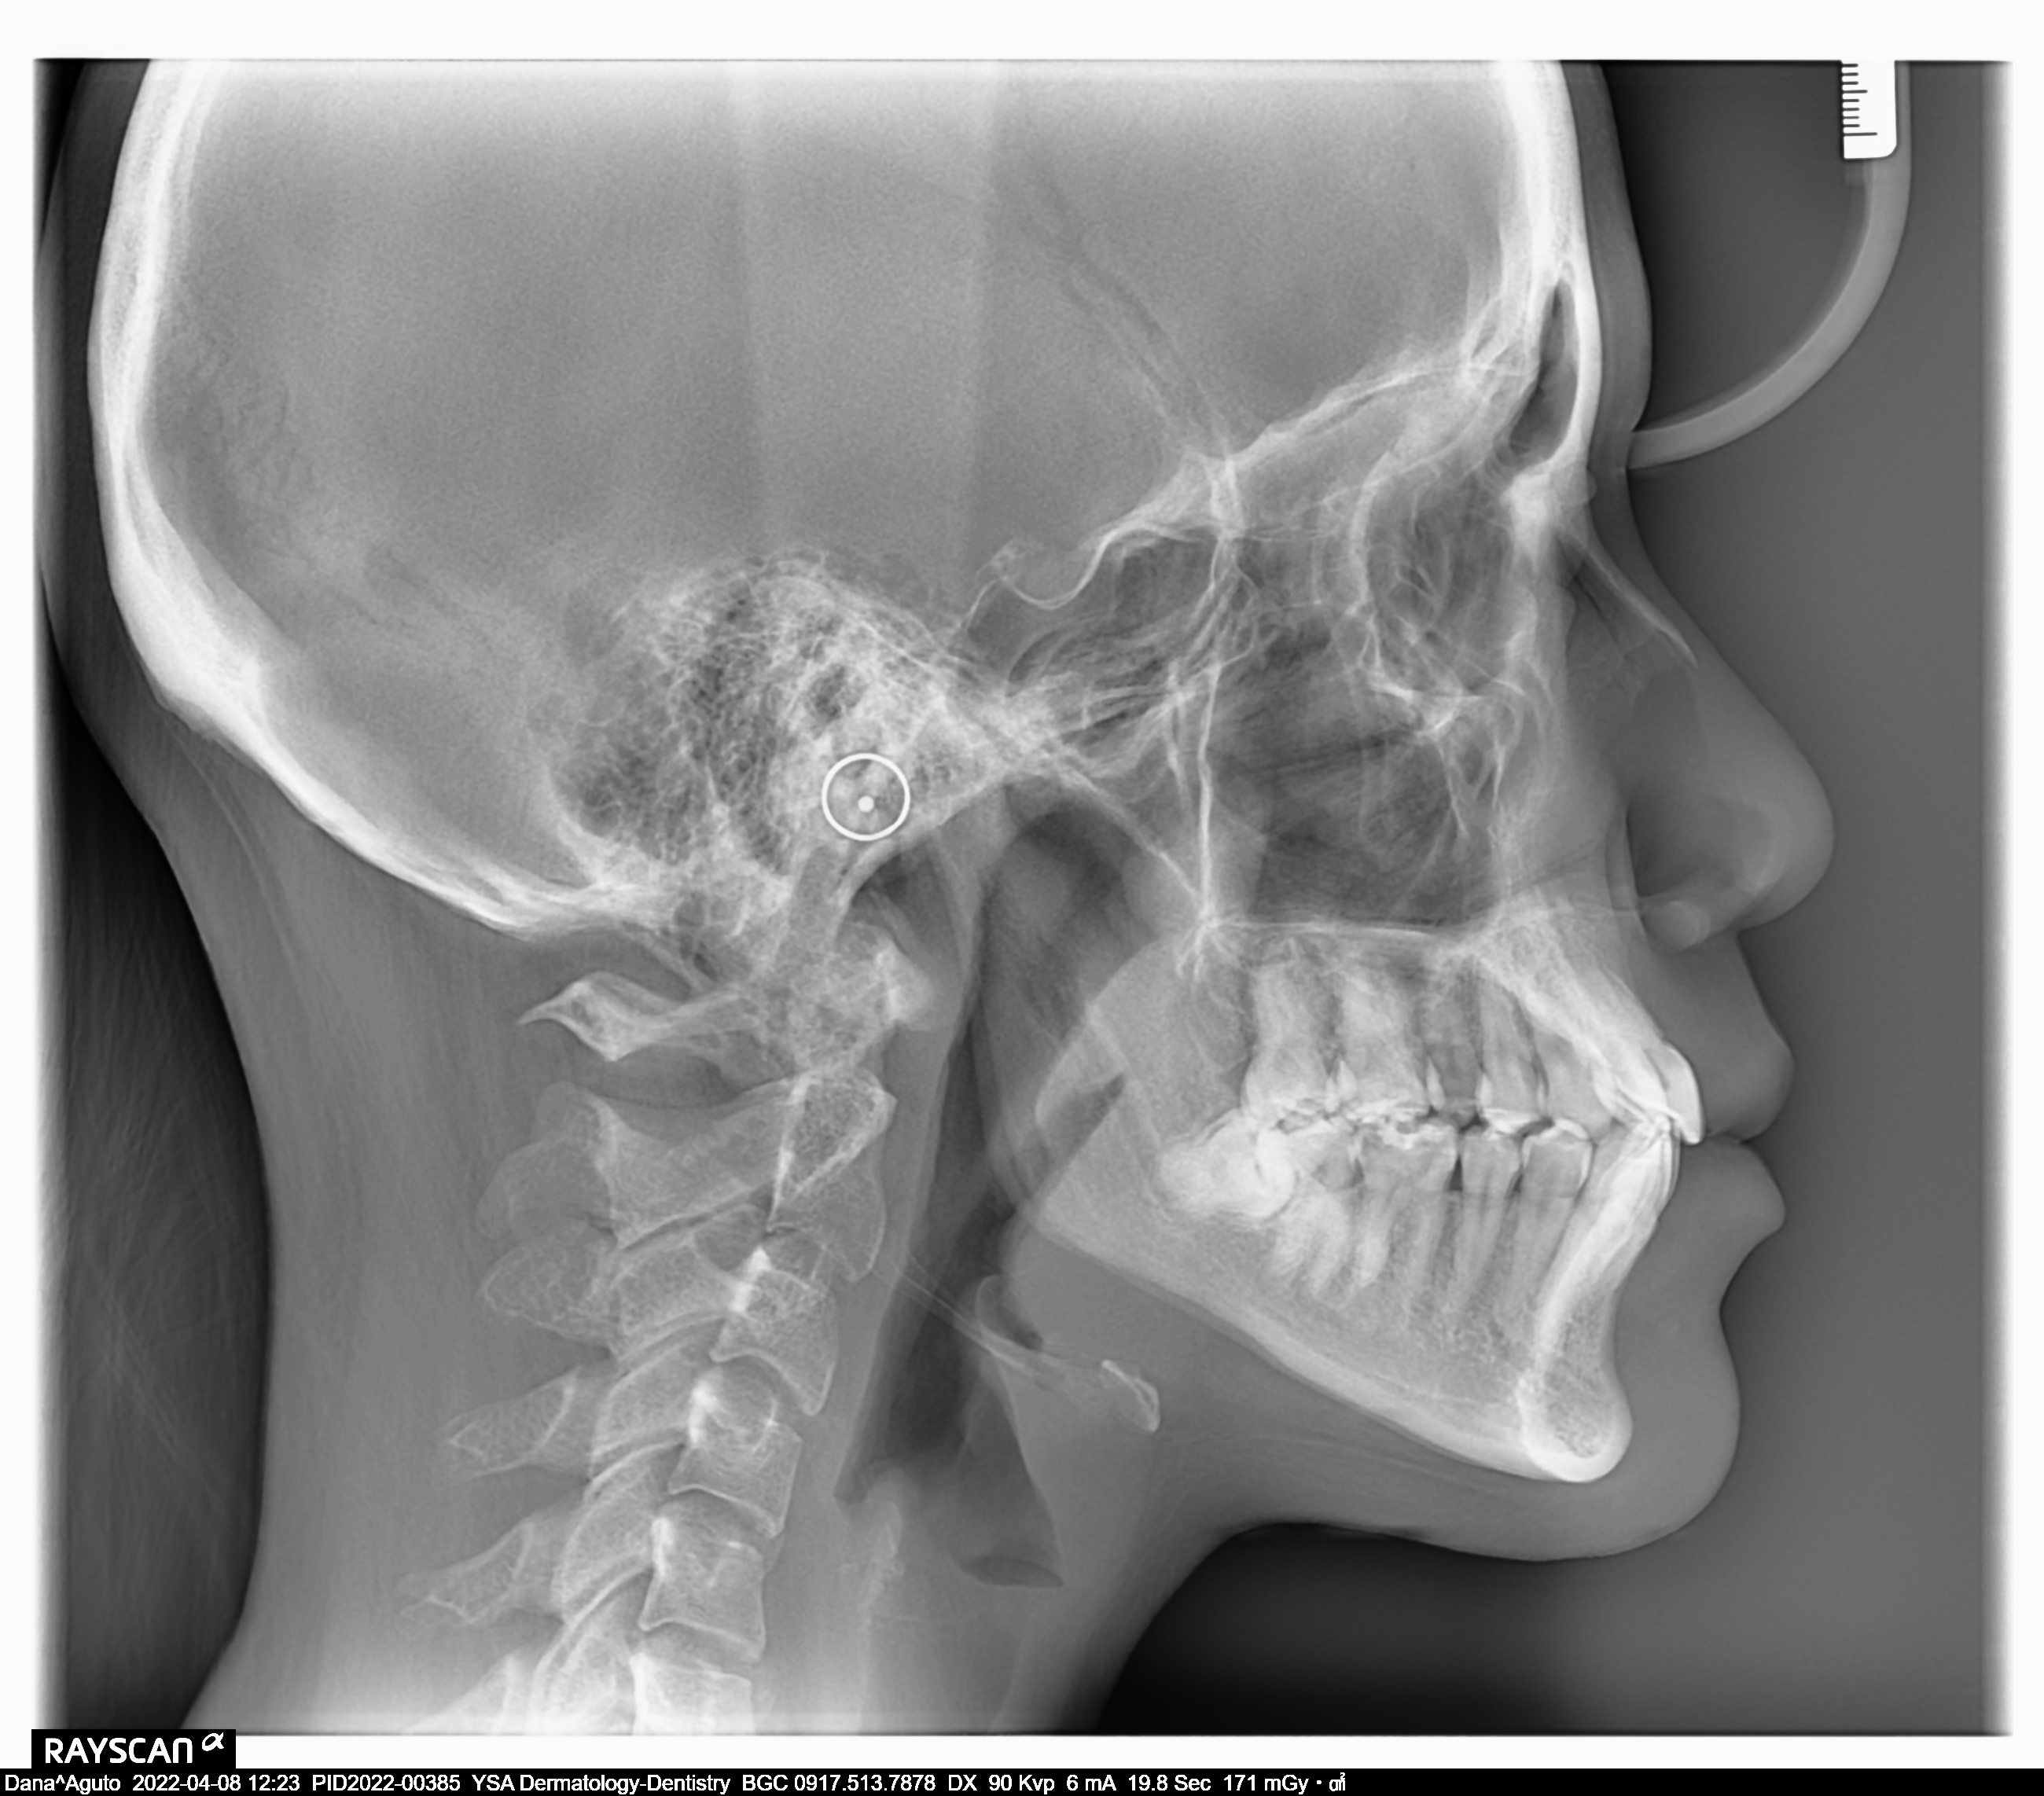

Edit Record Check our patient data records. Add patient information Patient Info Profile picture Last Name First Name Middle Name Birthdate Age Street Barangay City Country Zip Code Contact number Email Procedure 4/8/22- check up ***pano/ ceph ***#46 exo presence of lip tie 04/02/22 odontectomy 48/38- class 3/ mesioverted exo 46/ tongue tie/ ankyglossia frenectomy (laser) pt under IV CS Ozone therapy ****ff up after 2 weeks/ ***for orthodontic treatment 06/16/22 LC 24 OD/ CAOH LC 47 M op/ OZONE 1/11/23- Adj , 16niti Upper, Rotational Wedge # 42D , reattached #35 11/04/22-OP/LC 15,36,26,/mta/XRAY 11/16/22-InsOfBraces/Niti 14/14(MBT0.22) 12/07/22-adj 01/11/23- adj 04/12/23- same wire U/ Lower NiTi 16/ reattached #34,15/IPR between #32-33 05/05/23- U same wire; L SS-16; Resto #14DO, #15MOD, #16D 06/07/23- Informed Consent Resto #14DO (redo) Ortho UL same wire Remove RW #33 Monkey elastics #13-#23-#33-#43 07/19/23- Lc 36 occusal, lingual 18 ss U 18ss l rw 33 distal 08/18/23- 09/15/23- same wire #22 extrude 10/13/23 - adjustment, same wire - RW on #12 mesial 12/13/23-16X16 L -Penguin Cross Elastic -Upper to Right -Lower to left 01/12/24- adjustment same wires X-elastics on posterior Pms FOR removal on APRIL 02/21/24 same wire chain upper and lower rabbit to 3's to 4's 03/22/24 same wire rabbit 43 to 25 chipmunk 13 to 45 RW #45 distal 04/19/24 Removal of braces for retainers( vacuumed retainers) OP w/ flouride impression U/L 07/19/25 op with air polisher 03/18/26 Summer smile promo LC #14 - M,O, D + caoH + GI #15 - M,O,D + desen #16- M, O, Li + caoH + GI 03/26/26 Redo 04/08/26 check up 05/14/26 LC #16- fiber + mta File dana46.jpg File 2 file_0001_1_2.jpg File 3 file_0001_3.jpg File 4 dana_aguto.jpg File 5 dana_aguto_02.jpg File 6 dana_aguto_03.jpg File 7 dana_guto_04.jpg File 8 img_20240406_103512.jpg File 9 File 10 File 11 File 12 File 13 File 14 File 15 File 16 File 17 File 18 File 19 File 20 Retain Record Retain Record Yes No Save Your Changes